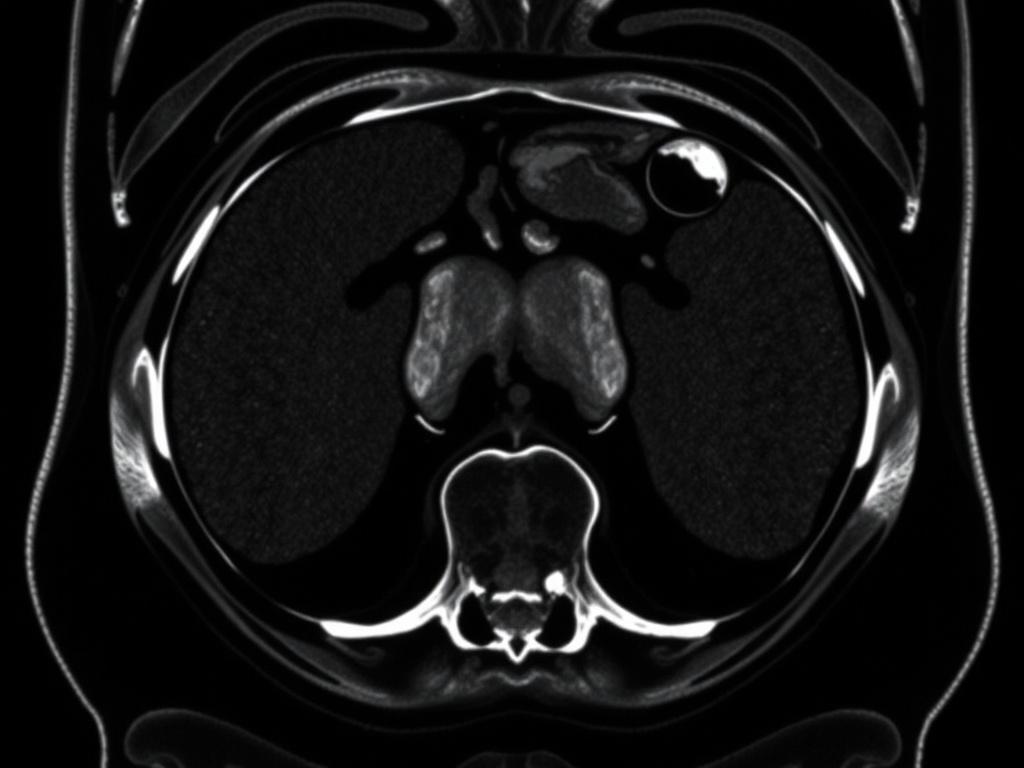

Для брюшной полости это особенно полезно: печень, желчный пузырь, поджелудочная железа, селезенка, почки и сосуды — все это можно рассмотреть в деталях. В отличие от УЗИ, МРТ меньше зависит от опыта оператора и от газов в кишечнике. И, что важно, МРТ не использует ионизирующее излучение, оно безопаснее по сравнению с компьютерной томографией, если речь о частых исследованиях.

Что может показать МРТ: конкретные примеры

Чтобы понять практическую пользу, полезно представить, какие состояния чаще всего выявляются с помощью МРТ брюшной полости. Ниже — таблица с примерами и пояснениями, что именно видит томография.

| Патология | Что показывает МРТ | Практическое значение |

|---|---|---|

| Опухоли печени | Локализация, характер васкуляризации, дифференциация доброкачественное/злокачественное | Планирование биопсии или операции |

| Хронический панкреатит | Изменение структуры поджелудочной, кисты, стенозы протоков | Выбор тактики лечения, оценка риска осложнений |

| Сосудистые аномалии | Степень поражения сосудов, тромбозы, портальная гипертензия | Определение необходимости интервенционной терапии |

| Метастазы | Мелкие и множественные очаги в паренхиме органов | Стадирование и выбор схемы лечения |